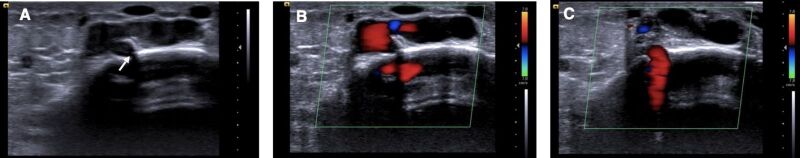

Anomalous intraosseous venous drainage causing pretibial varices is a rare and little-known cause of varicose veins in the lower limbs (LL). We report the case of a 49-year-old male patient with chronic pain associated with large pretibial varicose veins and mild edema of the left lower limb, with no skin changes or history of previous treatment. Vascular ultrasound identified a dilatated intraosseous vein of the tibia with reflux draining to an incompetent bone perforating vein and subcutaneous varicose veins. Bone perforating veins must be carefully investigated in the presence of atypical non-saphenous and recurrent varicose veins using vascular ultrasound, which demonstrates the periosteal defect in the tibia and presence of reflux that feeds the pretibial subcutaneous varicosities. Recognizing this rare entity avoids diagnostic errors and is essential for the most appropriate treatment.